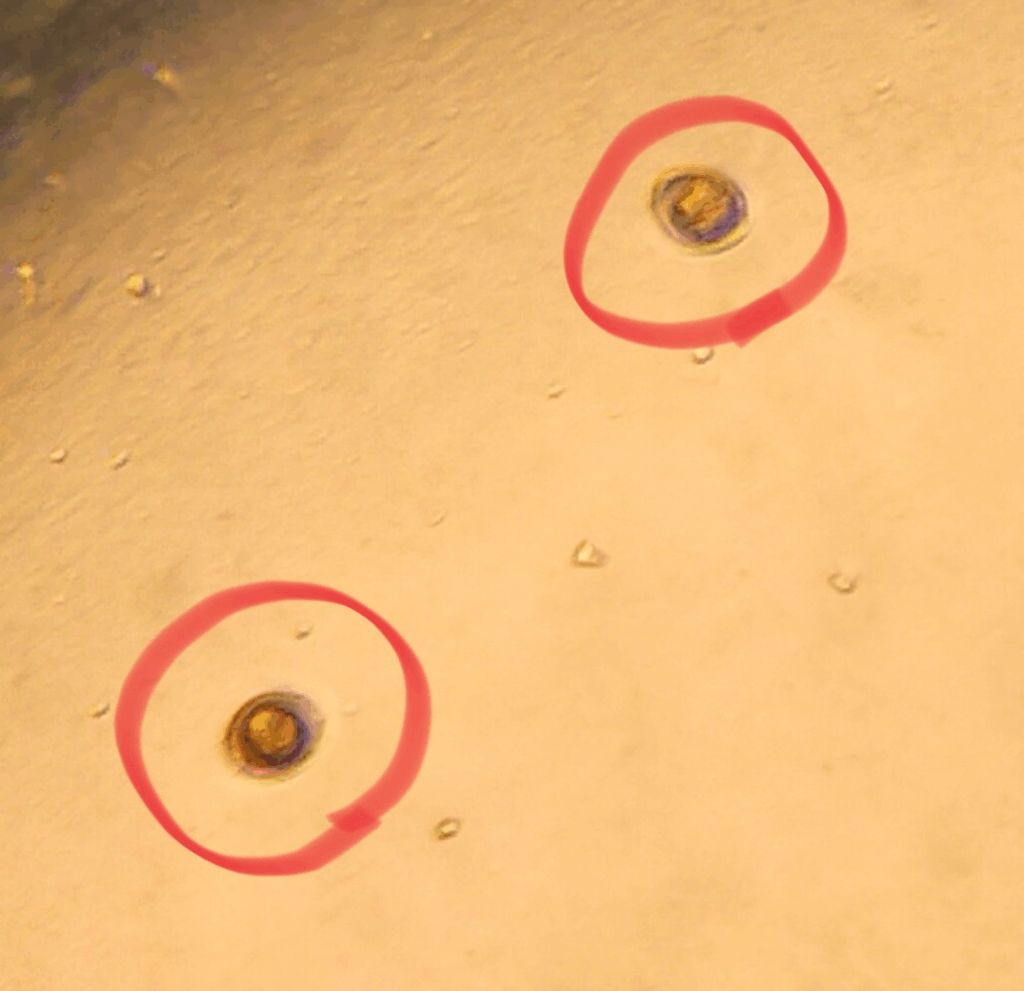

実際の虫卵写真イメージ

以下のように、検便で顕微鏡下に虫卵・原虫が見つかることがあります:

新患の3歳雌猫ちゃん、数年前から下痢。今まで整腸剤でよくなったり悪化したりを繰り返していたそう。便を持参したため「虫卵検査」をしたところ、コクシジウムがみつかりました。